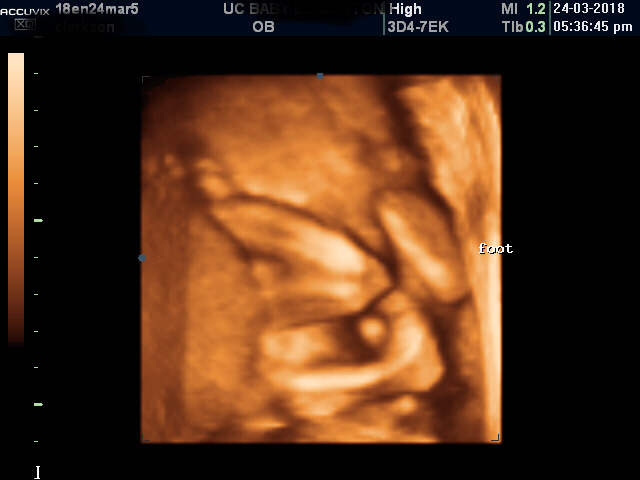

I had a 3D ultrasound at 20 weeks, the tech said boy. She showed me the penis however I forgot to ask to see the scrotum as well nor did I see a potty shot. Can you confirm this is a boy please?Attachment 39128Attachment 39129Attachment 39130